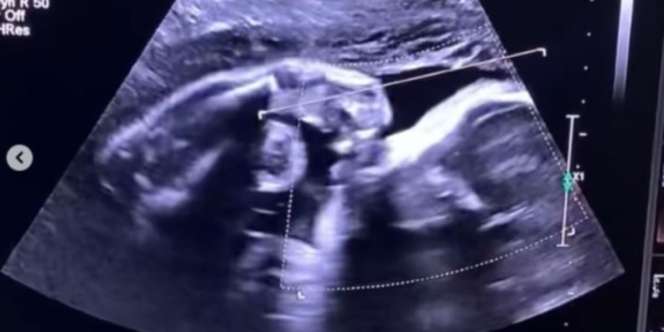

Ia mengatakan bahwa hatinya merasa bahagia saat melihat anak yang dikandungnya dalam keadaan sehat. Bahkan sang anak terlihat bergerak aktif saat menjalani USG.

“ Aku seneng banget pas usg bayiku gerak-gerak,” tulis calon ibu tersebut.

Namun, kesedihan itu langsung sirna berubah menjadi bahagia saat ia periksa usg dan melihat anak di dalam kandungannya menggerakkan tangan seperti sedang dadah ke ibunya.

Seolah bayi itu ingin memberitahu bahwa keadaannya di dalam baik-baik saja, sehingga sang ibu tidak perlu sedih dan khawatir lagi. Saking bahagianya, wanita ini sampai menangis saat melihat usg anaknya.